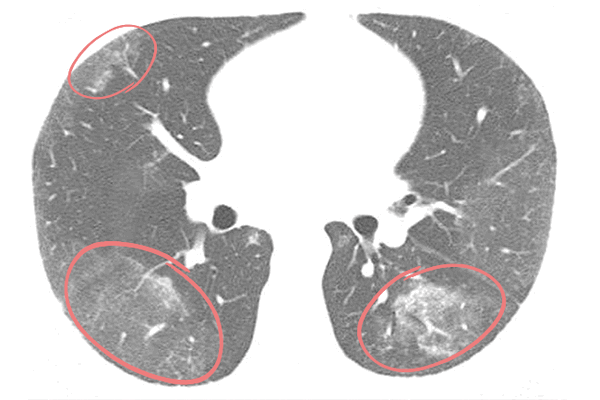

По данным актуальных исследований, публикуемых в журнале Radiology, вирусная пневмония, вызванная COVID-19, чаще всего проявляется на КТ изображениях в виде двухсторонних затемнений по типу «матового стекла» и уплотнений легочной ткани, например, утолщения альвеолярных перегородок. На томограммах это, напротив, более светлые участки, поскольку они свидетельствуют о повышенной плотности легочной ткани, а она хуже пропускает рентгеновские лучи.

Наличие одиночного очага поражения по типу «матового стекла» в правой нижней доле легкого может быть интерпретировано как начальное, самое первое проявление вирусной пневмонии.

«Матовые стекла» считаются основным признаком поражения легких при пневмонии. Так называют участки легочной ткани, в которых альвеолы заполнены жидкостью — это инфильтраты. Название отсылает непосредственно к визуализации этого признака при лучевой диагностике. Уплотнения по типу «матового стекла» напоминают беловатый налет, легочная ткань — светлая.

«Матовые стекла» при коронавирусе обычно локализуются с обеих сторон (двусторонняя пневмония) в нижних и боковых отделах, ближе к плевре либо сконцентрированы вокруг бронхов. При этом сохраняется видимость сосудов, бронхов и их стенок. По количеству и размерам инфильтратов определяют степень поражения легких.